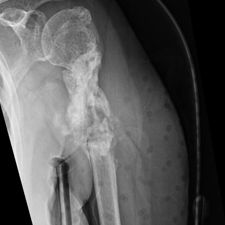

She was advised of the need to do some sort of stabilization which is necessary since the use of low-dose ultrasound has not helped in the healing process. She was unwilling to have any further operative intervention and sought further options. Eventually, she agreed to a fourth procedure of intra-medullary nail stabilization of the fracture and had this carried out in April 2011. An intramedullary nail was inserted in an antegrade manner and she has since gone on to heal the fracture site completely and has regained most of the function of the upper limb with no pain.

This case illustrates the possible complications that can occur with any surgery but also our commitment to our patients by sticking with them and making sure that a positive outcome is had despite the many challenges that may arise.